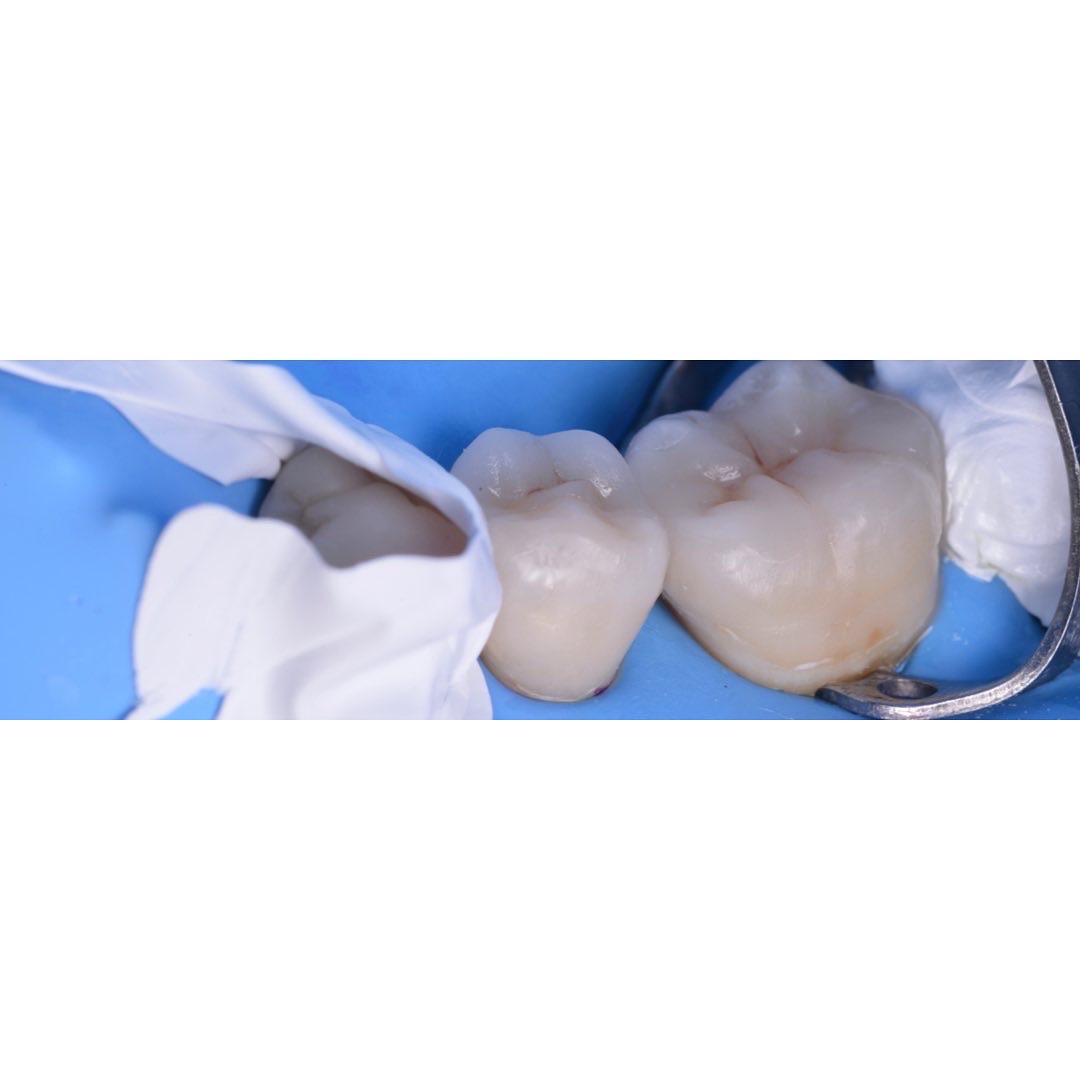

治療後